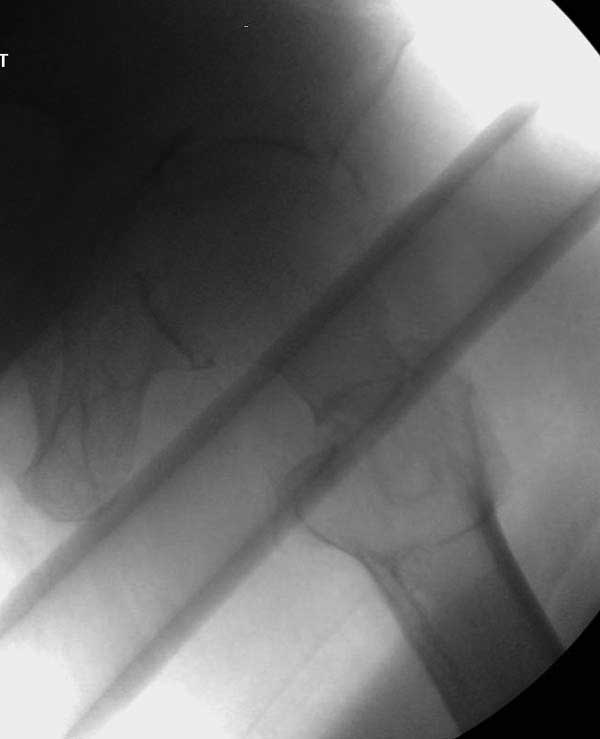

Прилагаю снимок сделанный еще в стационаре через 2 недели после операции.

Сеньоры-пэры ревизировали гвоздем, шуруп поставили по той же дорожке, только поглубже. Да еще и bone graft не пожалели. "Результат" уже был через 2 дня.

Если сохранять головку - думаю надо было в валгусе фиксировать перелом гвоздем, или DCS, т.к. все-равно разрезали, чтоб достать DHS.

Первые снимки показывают технические погрешности установки DHS. Не была достигнута репозиция, конечность в флексии и шейка в ротации. Сегодня все меньше обращают внимание на параметры для оценки репозиции (S контуры Lowell в обеих проекциях и Garden Alignment Index, в норме 155 и 180 градусов), хотя такие простые тесты помогли бы дорепонировать смещение. Винт находится сзади в головке, что при нагрузке поменяет вектор и вместо компрессии в линии перелома срежет головку-Cut Out!

Вторая операция- это фаза сохранения головки бедра. Желательно приложить все усилия и сохранить головку, но, как видно, “фиаско” продолжается. Здесь вместо нейтрализации сил между медиальной и латеральными сторонами была попытка удержать варус. Варус не удержать ни деротационными шурупами о котором говорили и не костными стружками вбитые в шейку, потому что вся нагрузка упирается в головку.

Как отметил Евгений, 95 degree Blade Plate Fixed Angle device расчитана на восстановление взаимоотношении между головкой и диафизом, а все остальные фиксаторы (Gamma, Afifuxus и др.) работают за счет нагрузки в верхнем полюсе головки. Верхний полюс успели разрушить, и в головке единственное место, который смог бы удержать широкий клинок конструкции, это медиально-низкий сегмент. После установки клинка засчет дистракции можно удлинить конечность на 15мм, а добавленный в дефект ауто-графт закончил бы дело.